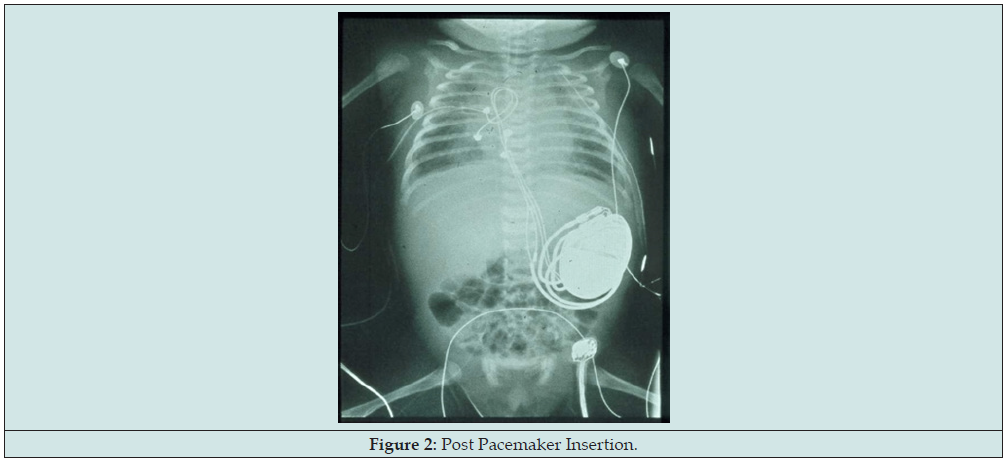

Fetal cardiovascular study still showed atrioventricular dissociation, this time ventricular rate now noted at 50 per minute. Atrial rate was normal at 136 per minute. Chamber sizes remained within normal limits for fetal age with normal Z score indicating absence of heart failure despite deterioration of fetal heart rate. Ventricular wall motion, contractility, and systolic function remained good. Still no signs of hydrops fetalis noted at this point. But on the 36 weeks’ gestation, drop in the fetal heart rate was noted, now to 50bpm hence the mother was immediately admitted for the proposed EXIT procedure and AS’ pacemaker insertion. Primary cesarean section under general anesthesia was done at 36 weeks AOG. Upon delivery, EXIT procedure, epicardial pacemaker insertion via median sternotomy, and left femoral artery cannulation were performed and the patient was then transferred to the Neonatal ICU (Figures 1 & 2). Patient’s APGAR score is 2, 7 with a maturity rating of 36 weeks AOG. Pertinent physical examination revealed a bradycardic and pale newborn, no gross deformities, no murmur, no hepatomegaly, no cyanosis with cold and fair pulses [4].